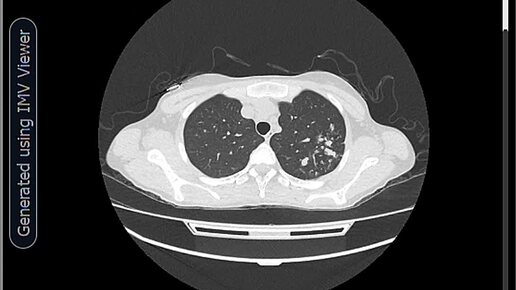

КТ ОГК-туберкулез легкого.